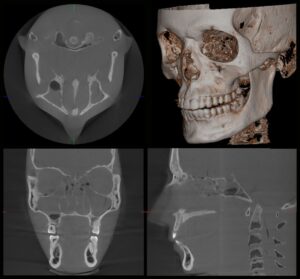

【CT画像(例)】

断面・3D再構成で位置関係を立体的に把握できます。